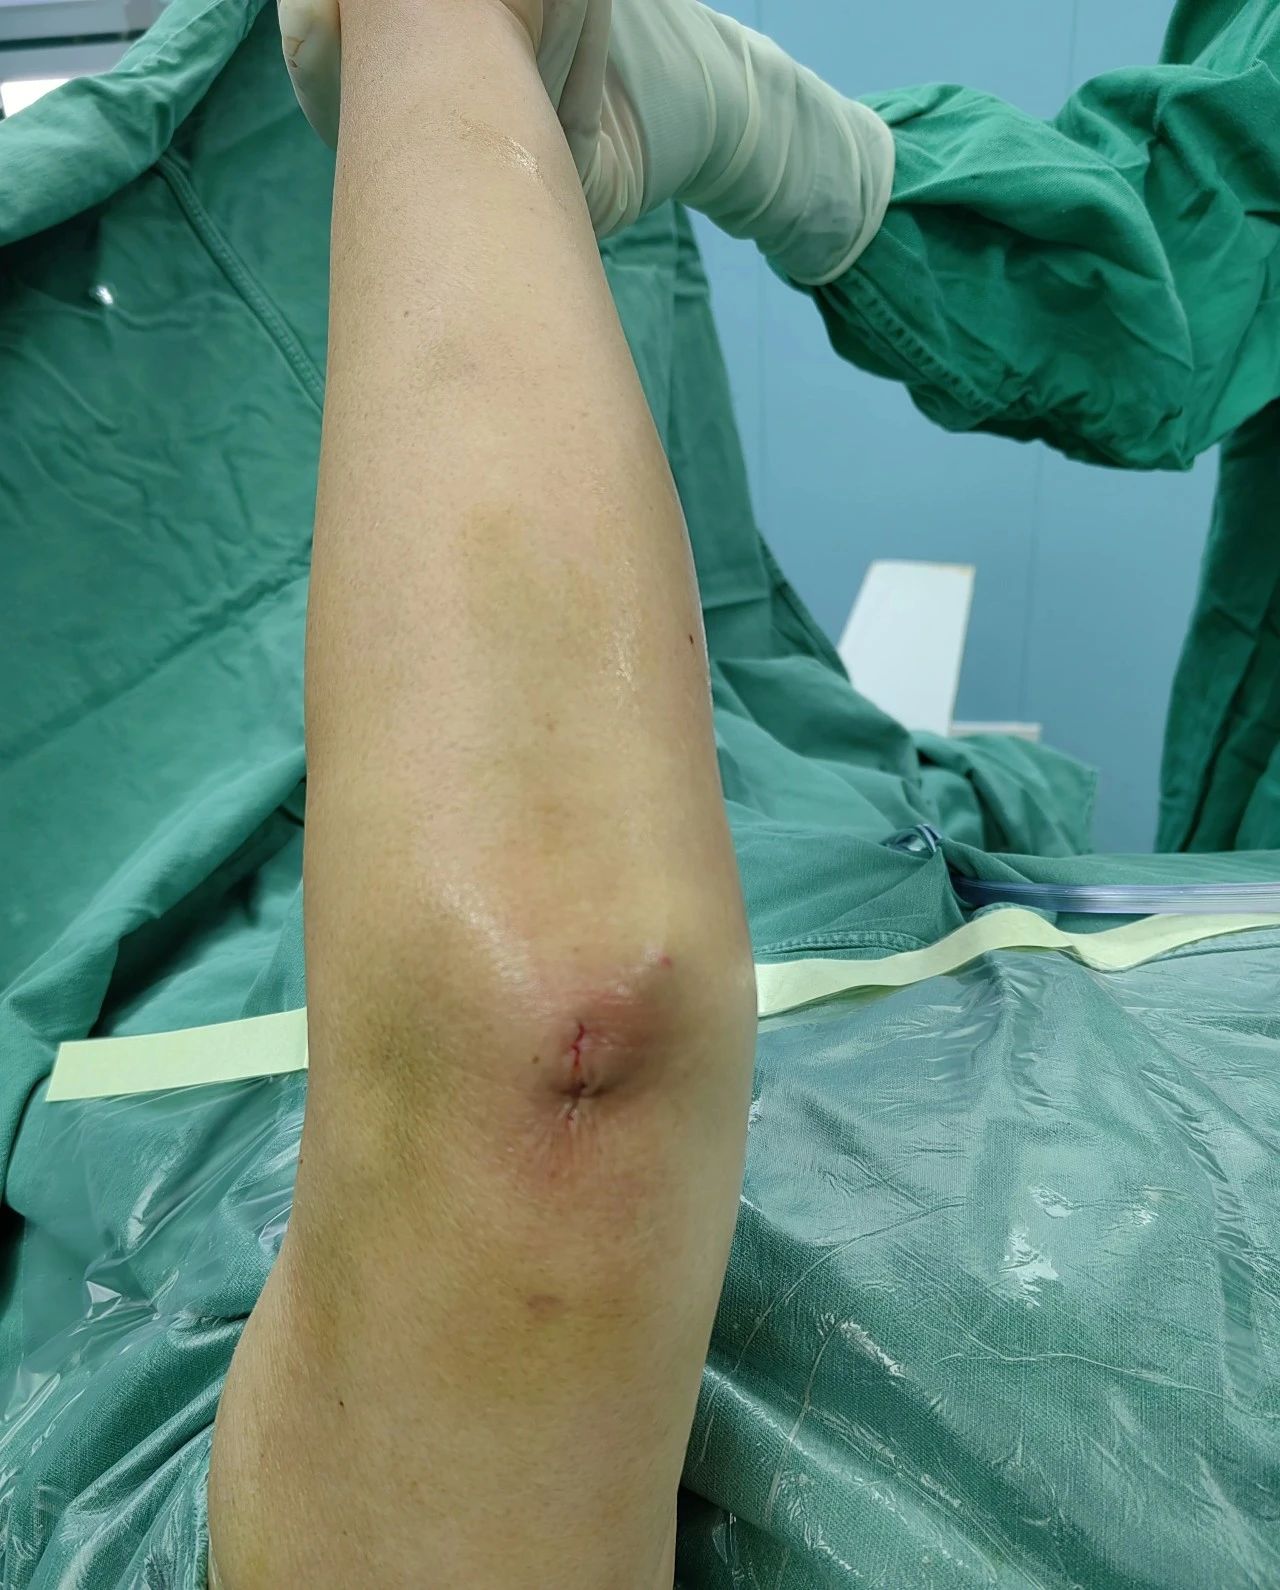

手术在孙杰院长的指导下,由骨三科团队默契配合,精准操作,仅通过几个小切口,便成功完成骨折复位和髓内钉固定。 手术创伤小、出血少、恢复快、疼痛轻,术后患者恢复良好,对手术效果非常满意。